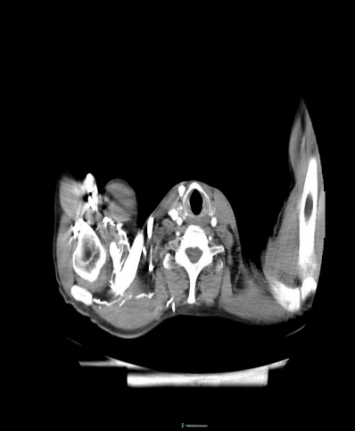

患者情況 + + + + 患者楊先生,57歲,既往肺結(jié)核病史,因2+月前因“吞咽困難”未予重視,出現(xiàn)進(jìn)食后嘔吐,嘔吐物為胃內(nèi)容物,近3月來體重下降約“10kg”,就診于外院,胃鏡提示食管占位鱗狀上皮重度異性增生,于2024年7月29日以“食管占位”收入我科繼續(xù)治療,頸部增強(qiáng)

CT提示食管下段鱗癌。結(jié)合患者既往肺結(jié)核病史肺功能及身體情況差。 術(shù)前相關(guān)影像學(xué)檢查 術(shù)前詳細(xì)討論,做好充分準(zhǔn)備 + + + + 術(shù)前,徐靜峰主任邀請(qǐng)麻醉科、腫瘤科、結(jié)核科以及輸血科等多個(gè)學(xué)科的專家進(jìn)行深入討論,一致決定為患者執(zhí)行一項(xiàng)頸胸腹三切口食管癌根治術(shù)。這是一次技術(shù)要求極高的四級(jí)手術(shù),術(shù)前準(zhǔn)備工作不僅包括精確的影像學(xué)和病理學(xué)評(píng)估,還必須應(yīng)對(duì)患者所面臨的多種基礎(chǔ)疾病和潛在并發(fā)癥的挑戰(zhàn)。 手術(shù)圓滿成功,彰顯團(tuán)隊(duì)實(shí)力 8月20日,徐靜峰主任團(tuán)隊(duì)在麻醉科和手術(shù)室的完美協(xié)作下,成功為楊先生在全身麻醉狀態(tài)下執(zhí)行了胸腹腔鏡聯(lián)合頸胸腹三切口食管癌根治術(shù)。手術(shù)過程中,麻醉順利進(jìn)行,手術(shù)也順利完成,術(shù)中出血量控制在約50毫升,達(dá)到了預(yù)期的理想效果。這次手術(shù)不僅彰顯了我院胸外科技術(shù)的進(jìn)一步提升,也展示了徐靜峰主任團(tuán)隊(duì)在食管癌治療領(lǐng)域的精湛技藝、細(xì)致護(hù)理,以及各科室之間卓越的協(xié)作能力。 術(shù)后精心護(hù)理,攻克疑難病癥 患者護(hù)理團(tuán)隊(duì)通過十二指腸營(yíng)養(yǎng)管為患者提供腸內(nèi)營(yíng)養(yǎng),注入流質(zhì)飲食。他們強(qiáng)化了對(duì)呼吸道、胃腸道、傷口及引流的管理,并進(jìn)行了細(xì)致的護(hù)理觀察。術(shù)后第二天,患者便能夠下床活動(dòng),到了第七天,患者已能正常經(jīng)口攝入流質(zhì)飲食。在二十天后,患者順利出院,期間未出現(xiàn)任何術(shù)后并發(fā)癥。這一過程表現(xiàn)出創(chuàng)傷小、風(fēng)險(xiǎn)低、出血少以及預(yù)后優(yōu)良的特點(diǎn)。 市公衛(wèi)中心胸外科團(tuán)隊(duì)將持續(xù)以患者為核心,提供卓越的醫(yī)療技術(shù)和一流的??谱o(hù)理服務(wù),攻克更多復(fù)雜病癥,為廣大的患者群體帶來新的希望。 胸外科小科普: ? 食管是將食物從口腔傳輸?shù)轿覆康墓艿馈?/p> 食管癌又叫食道癌好發(fā)于食管內(nèi)壁的上皮細(xì)胞,是作為世界常見的惡性腫瘤之一,全球約有40萬新發(fā)病例,約30萬人死于食管癌,中國(guó)是世界上食管癌發(fā)病率最高的地區(qū)之一,一般男性高于女性。 ? ? ? 發(fā)生食管癌的臨床表現(xiàn): 早期:1、梗咽感 2、胸骨后灼感 3、異物感 4、無癥狀; 進(jìn)展期:1、進(jìn)行性吞咽困難 2、嘔吐、3、后背疼痛 4、體重下降; 晚期:1、侵犯穿孔(疼痛、嗆咳、嘔血) 2、神經(jīng)受累(聲音嘶?。?3、消瘦、貧血、低蛋白 4、遠(yuǎn)處轉(zhuǎn)移。 什么情況會(huì)誘發(fā)食管癌:愛吃腌制食品、趁熱吃趁熱喝、煙酒不離手、遺傳因素。 在正常情況下,食管的耐受高溫在50-60,但對(duì)一般人來說,口腔覺得燙的時(shí)候,食物起碼是70左右了,超出了食管的承受能力。